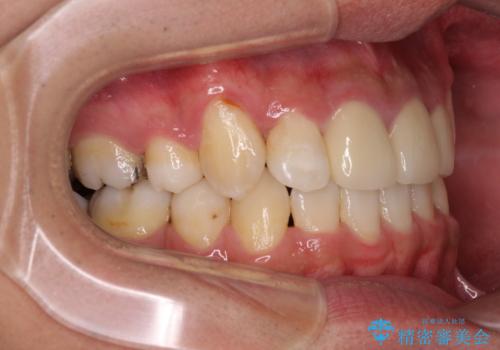

前歯の歯列が整ったことで、歯磨きが大変やりやすくなり、患者様には大変満足していただけました。

前歯は根管治療が必要な歯を事前に根管治療を行い、矯正治療後にオールセラミッククラウンにて補綴治療を行うこととしました。